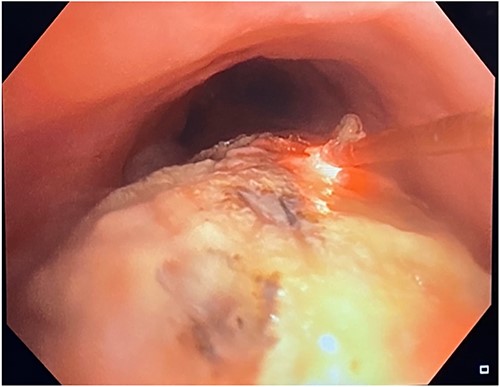

A 71-year-old female presented in May 2020 with a 6-month history of progressive dysphagia and weight loss. Her past medical history was significant for recurrent ductal carcinoma in situ of the left breast. She was a never smoker. Esophagogastroduodenoscopy (EGD) showed a proximal circumferential mass with friable mucosa and ulcerations at 15 cm (Fig. 1A–D). Computed tomography (CT) imaging showed significant soft tissue thickening and luminal narrowing of the esophagus from the sternoclavicular joints to the carina (Fig. 2E). An esophageal stent was placed to support nutrition, which improved the patient’s dysphagia. Biopsy confirmed invasive SCC. Subsequent positron emission tomography imaging revealed 18-fluorodeoxyglucose-avid mediastinal, bilateral supraclavicular, and subdiaphragmatic lymph nodes. Bronchoscopy showed no evidence of tumor invasion into the airway.

(A–D) EDG images showing circumferential esophageal mass with friable mucosa and ulcerations. (E) CT chest showing marked soft tissue thickening with luminal narrowing in the upper esophagus, which extended to a level below the carina.